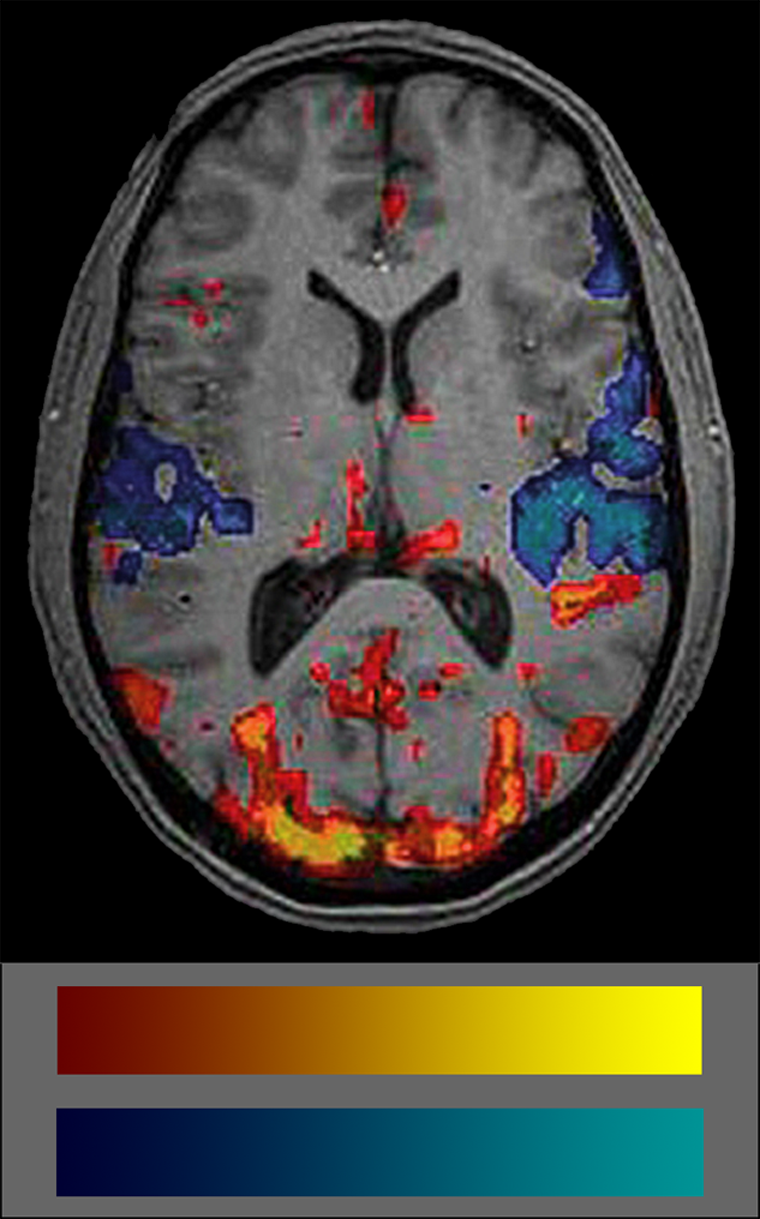

Commonly, BOLD data are shown coded in colors. Many users don’t really un­der­stand what the colors mean because they are not intuitive (Figure 11-15). The se­mio­tics of the commonly used BOLD color code is red-yellow colors for increased blood volume — which attract attention — and blue-cyan for decreased blood vo­lu­me which are easily put aside and overlooked. Thus, attention is commonly paid to blood flow increases but not to decreases which biases interpretation. Another pro­blem is the lack of any standard in color schemes of BOLD studies (for details on the use of color in medical imaging (cf. Chapter 15).

Figura 11-15:

fMRI image and color coding scale: red to yellow to indicate increased blood volume and dark blue to cyan to indicate decreases. The frequent absence of any color scale explication is a major set-back of most publications on BOLD imaging.

It is important to always keep in mind that the colored blots in BOLD images show sta­tis­ti­cal sig­ni­fi­can­ces of blood supply, not of brain activity.